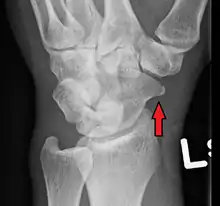

A subtle scaphoid fracture

Radiolucency around a 12 days old scaphoid fracture that was initially barely visible.[13]